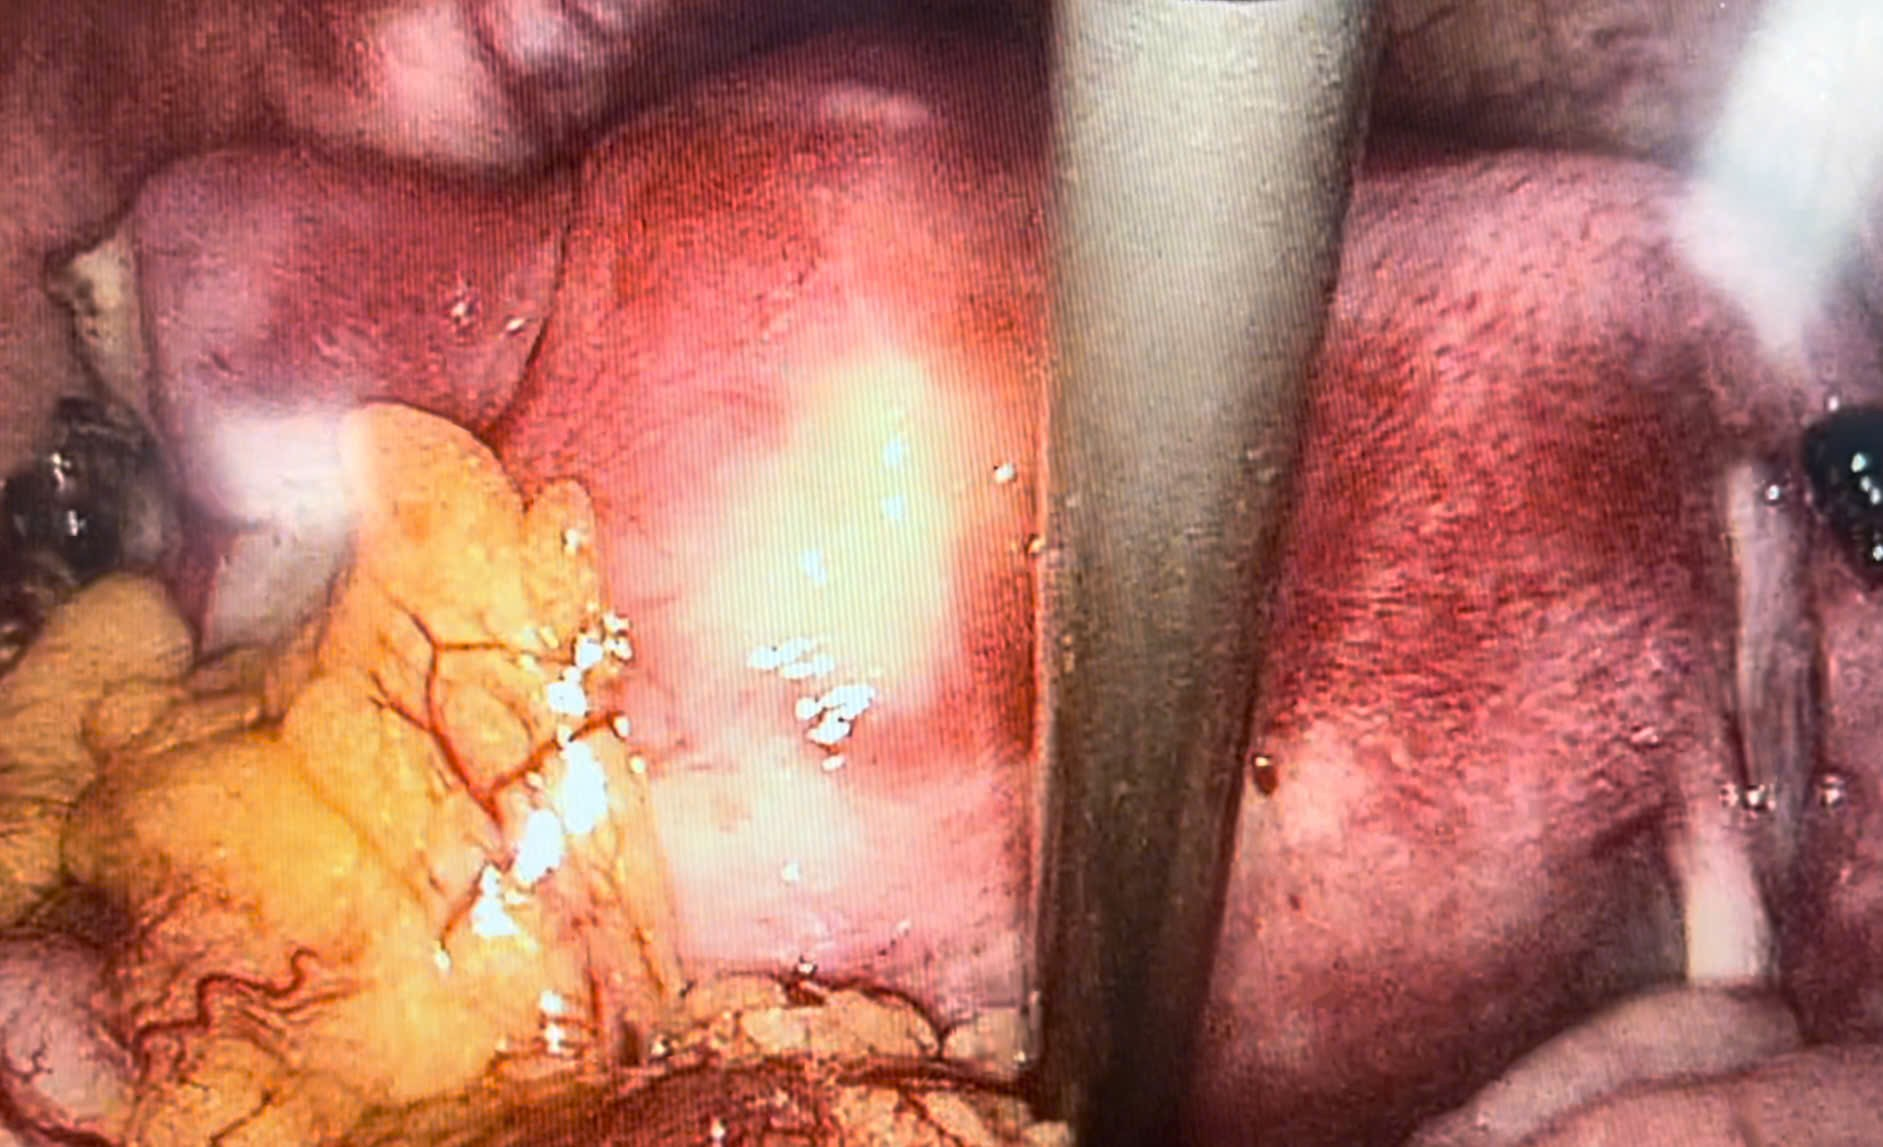

Phương pháp điều trị: phẫu thuật nội soi cắt khối thai ngoài

Hình 4. Hình ảnh tử cung phần và 2 phần phụ sau mổ

Bệnh nhân được phẫu thuật ngay: